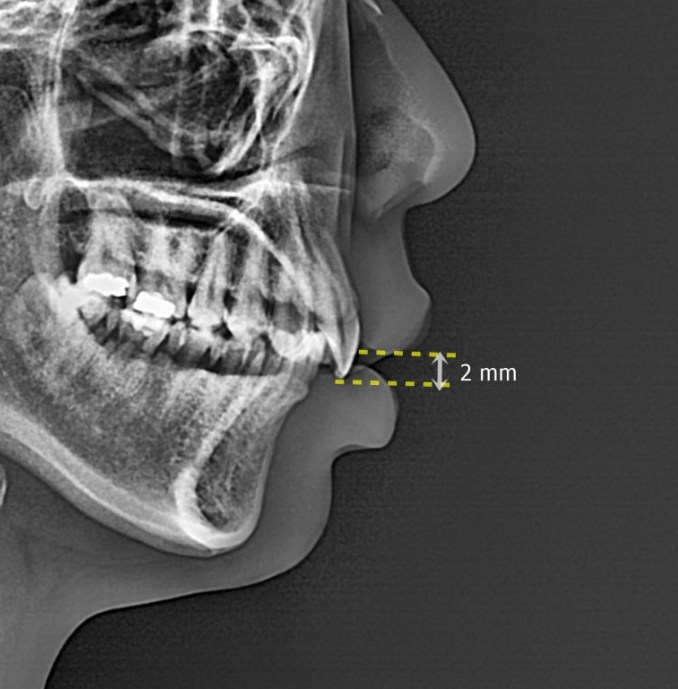

옆모습 엑스레이에서 윗입술과 앞니끝 사이의 수직 거리를 앞니노출도라고 하고 2mm가 정상입니다.

만약 이 부분이 2mm 이상이라면

위 앞니와 잇몸이 전반적으로 아래로 내려와 있는 것으로 진단을 하고

교정치료로 앞니를 잇몸뼈속으로 올리는 함입 치료를 하면 거미스마일 해소가 가능합니다.